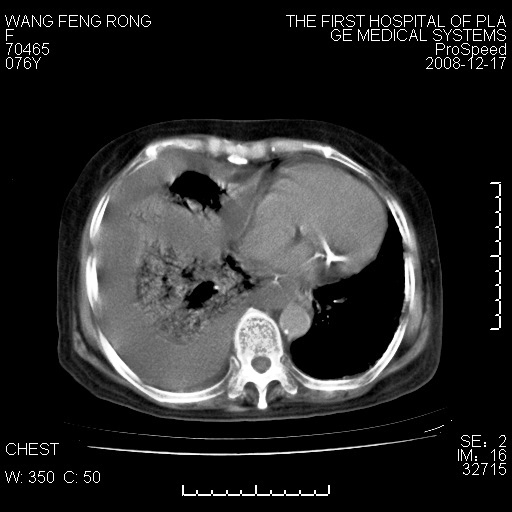

右肺大部实变,其内可见支气管影,但分支减少,宽窄不均,走行僵直,同侧胸腔大量积液;纵隔内见多发淋巴结影,但淋巴结大部有钙化;主动脉壁钙化;临床上病人咳嗽、消瘦。所以我考虑:1、结核(依据:右下肺实变,纵隔内淋巴结符合结核表现,同侧并发胸膜炎表现);2、支气管肺泡癌(依据:实变的肺组织内支气管分支减少,宽窄不均,走行僵直,没有把它放在第一诊断是因为没有看到明显肿大的淋巴结);3、动脉硬化(主动脉壁钙化就支持这个诊断)。

1)考虑两肺炎症感染;不排除肺泡癌可能。2)两肺间质纤维化。3)右侧胸腔积液。

病理结果,肺泡癌